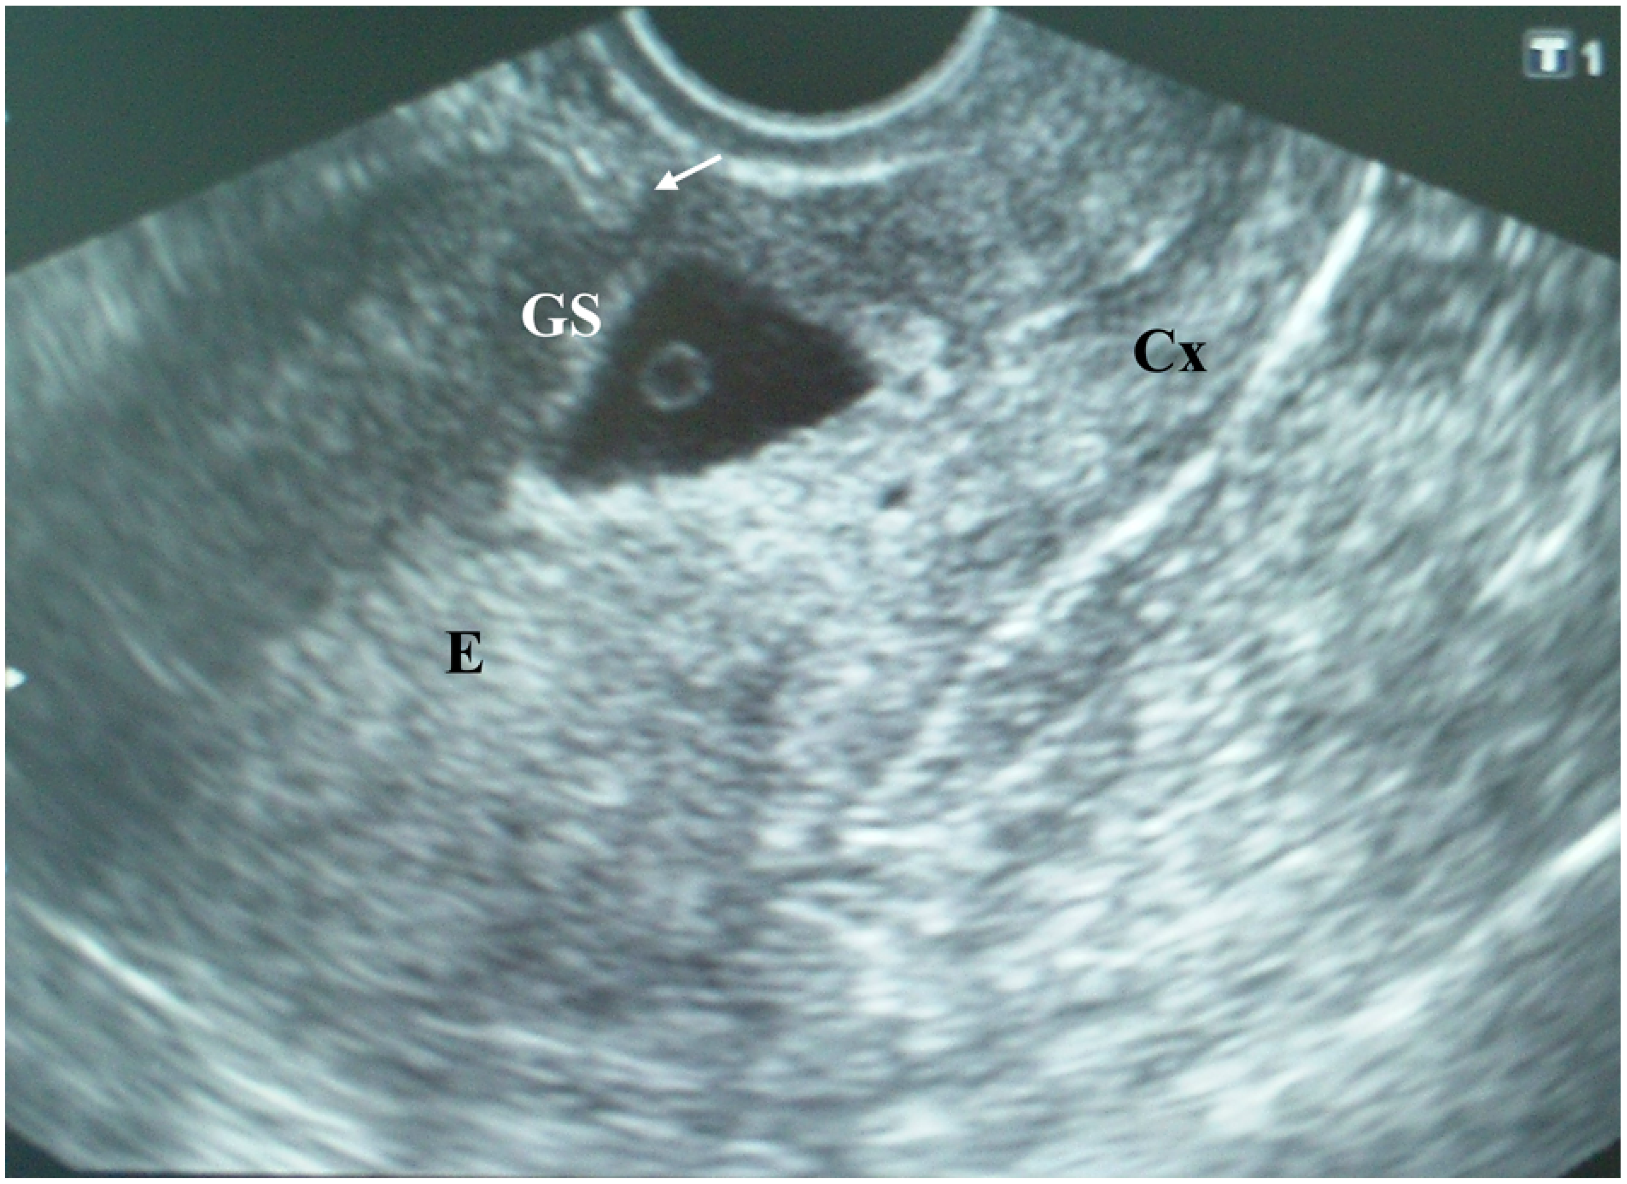

The patient’s laboratory results were within normal limits. Cesarean scar ectopic gravidity was suspected, and the patient was informed of the evolution to placenta previa, possibly to accreta, as well as of the associated risks. She was offered the option of termination. The patient, however, refused the termination of the pregnancy. Six days later, the patient was asymptomatic, and her abdominal pain disappeared, TVUS revealed a gestational sac containing an embryo with heart action and a crown–rump length (CRL) of 9.6 mm, which corresponded to 7 weeks and 1 day of gestation (Figure 2).

Figure 2.

Cesarean scar pregnancy: A gestational sac (GS) containing an embryo with heart action and a crown–rump length (CRL) of 9.6 mm, which corresponded to 7 weeks and 1 day of gestation.

The apparent larger thickness of the myometrial layer on the ultrasound examination performed during the eighth postmenstrual week (Figure 2) could be explained by the unequal thickness of the myometrial layer over the gestational sac along the cesarean scar and the development of the gestational sac toward the uterine cavity. Therefore, it seems that an ultrasound examination performed earlier in pregnancy is more accurate in predicting the severity of placenta accreta spectrum disorder.